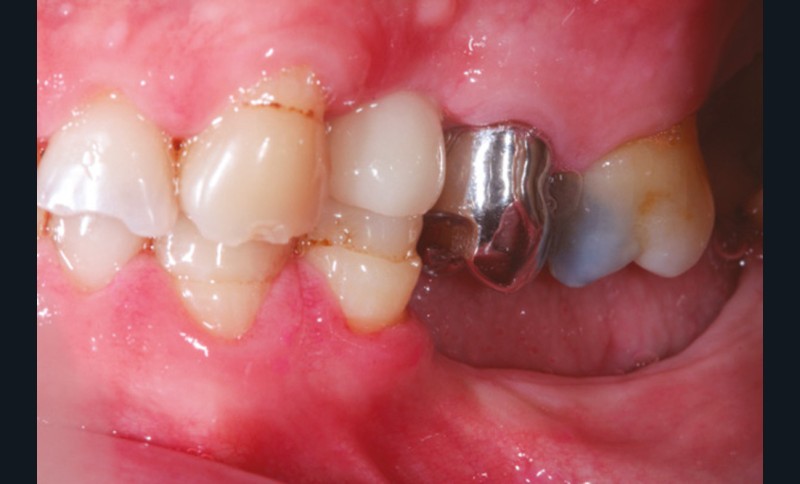

La version des dents distales peut aussi avoir des conséquences parodontales désastreuses : sur un parodonte réduit, une hypermobilité peut se développer, une poche parodontale peut aussi apparaître. Chez un patient parodontal, un « effet domino » est possible, des extractions non compensées diminueront donc le pronostic des dents restantes (fig. 7 à 9).